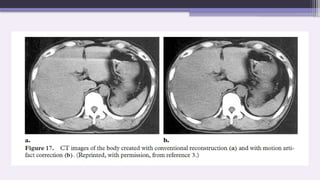

2. Adaptive Filtration

This software correction smooths the attenuation profile in areas

of high attenuation before the image is reconstructed.

A multi-dimensional adaptive filtration technique is used on

multi-section scanners.

For the small proportion of projection data that exceed a selected

attenuation threshold, smoothing is carried out between adjacent

in-plane detectors and between successive projection angles

while the z filter used in helical reconstruction is broadened for

high-attenuation projection angles to allow more photons to

contribute to the reconstruction